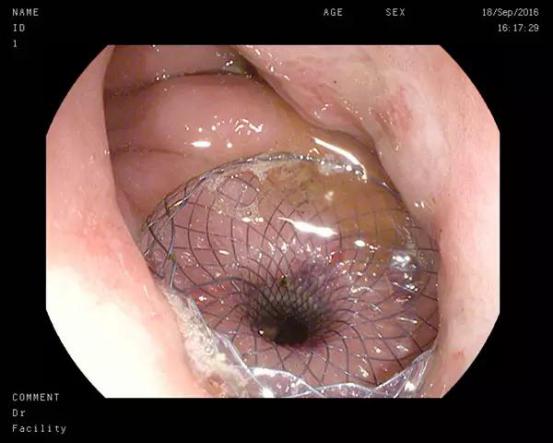

双蘑菇头支架被成功植入到胃壁和囊壁之间

此次患者郑某、耿某均于半年前发生胰腺炎,病情稳定后逐渐出现腹胀、进食后呕吐等梗阻症状,入院后经CT检查发现巨大胰腺假性囊肿形成。我院东院消化内科以张春清主任、张俊勇副主任医师为首的超声内镜介入团队,带领冯华主治医师、王广川主治医师,结合疾病特点和既往经验,反复研究琢磨,借鉴先心病室间隔缺损“封堵器”的原理,创新采用特制双蘑菇头覆膜支架代替传统胆道支架,通过膨大的双蘑菇头将胃壁和囊壁牢牢卡在一起,从而避免支架滑脱的可能,另外宽大的蘑菇头使术者可以轻松的操作鼻胃镜经支架中间孔道进入囊腔,进而对囊内坏死物质进行冲洗和清理,促进患者恢复。两位患者在植入双蘑菇头支架后,腹胀症状迅速缓解,即可正常饮食,经4周引流,复查CT囊肿基本消失,支架无任何移位,遂在内镜下将支架取出,胃壁创口愈合良好。